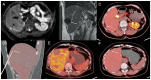

Neuroendocrine neoplasms (NENs) are rare and heterogeneous epithelial tumors most commonly arising from the gastroenteropancreatic (GEP) system. GEP-NENs account for approximately 60% of all NENs, and the small intestine and pancreas represent two most common sites of primary tumor development. Approximately 80% of metastatic patients have secondary liver lesions, and in approximately 50% of patients, the liver is the only metastatic site. The therapeutic strategy depends on the degree of hepatic metastatic invasion, ranging from liver surgery or percutaneous ablation to palliative treatments to reduce both tumor volume and secretion. In patients with grade 1 and 2 NENs, locoregional nonsurgical treatments of liver metastases mainly include percutaneous ablation and endovascular treatments, targeting few or multiple hepatic metastases, respectively. In the present work, we provide a narrative review of the current knowledge on liver-directed therapy for metastasis treatment, including both interventional radiology procedures and nuclear medicine options in NEN patients, taking into account the patient clinical context and both the strengths and limitations of each modality.